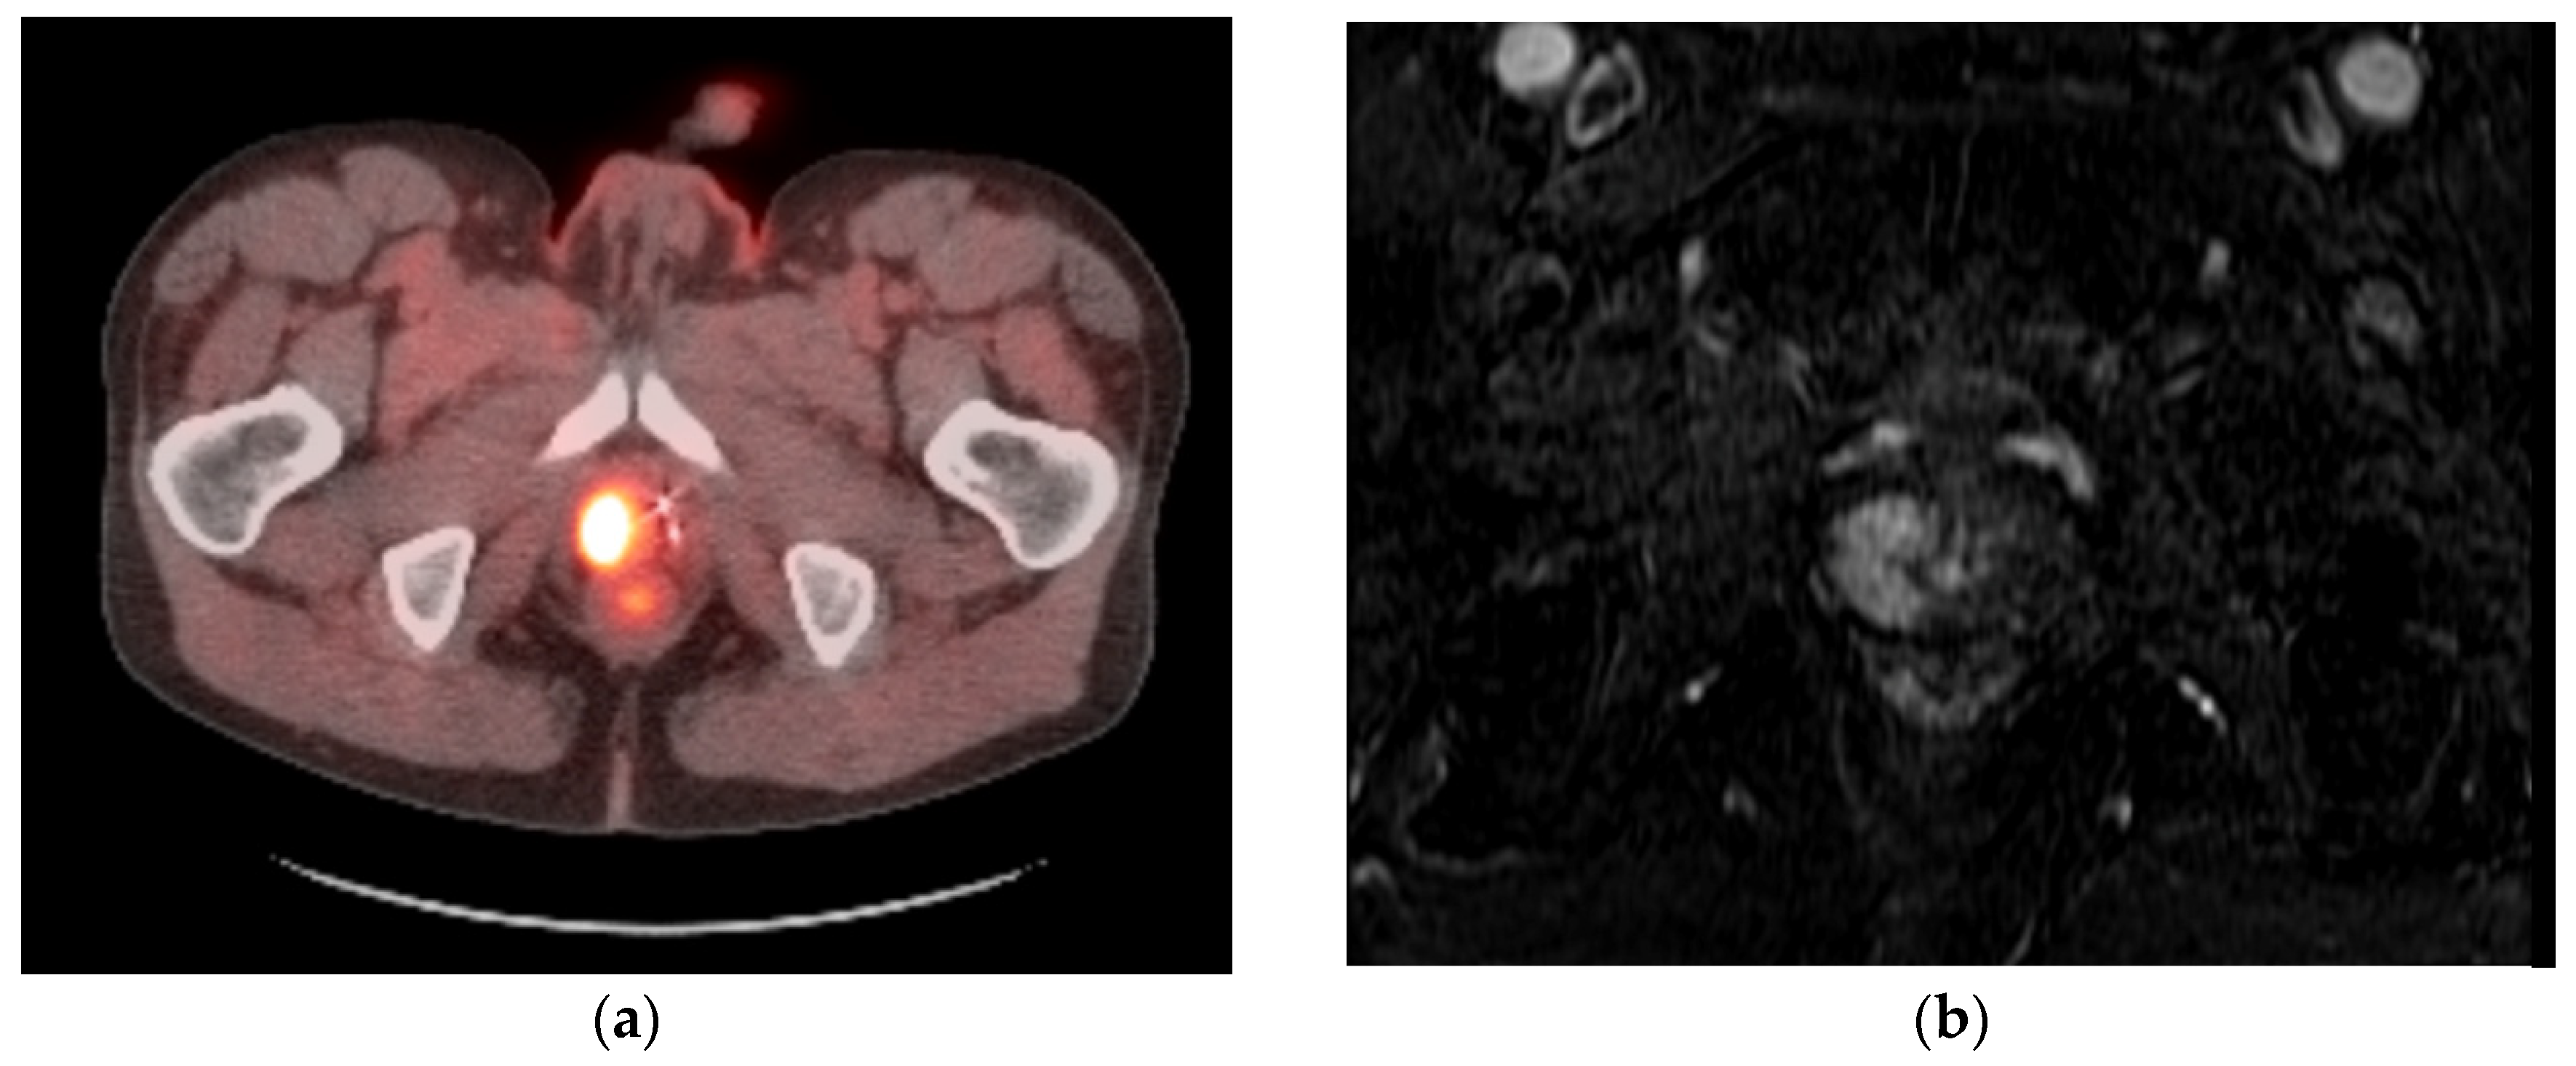

- Woodrum, D.A.; Kawashima, A.; Karnes, R.J.; Davis, B.J.; Frank, I.; Engen, D.E.; Gorny, K.R.; Felmlee, J.P.; Callstrom, M.R.; Mynderse, L.A. Magnetic resonance imaging-guided cryoablation of recurrent prostate cancer after radical prostatectomy: Initial single institution experience. Urology 2013, 82, 870–875. [Google Scholar] [CrossRef] [PubMed]

- Gangi, A.; Tsoumakidou, G.; Abdelli, O.; Buy, X.; de Mathelin, M.; Jacqmin, D.; Lang, H. Percutaneous MR-guided cryoablation of prostate cancer: Initial experience. Eur. Radiol. 2012, 22, 1829–1835. [Google Scholar] [CrossRef] [PubMed]

- De Marini, P.; Cazzato, R.L.; Garnon, J.; Tricard, T.; Koch, G.; Tsoumakidou, G.; Ramamurthy, N.; Lang, H.; Gangi, A. Percutaneous MR-guided whole-gland prostate cancer cryoablation: Safety considerations and oncologic results in 30 consecutive patients. Br. J. Radiol. 2019, 92, 20180965. [Google Scholar] [CrossRef] [PubMed]

- Overduin, C.G.; Jenniskens, S.F.M.; Sedelaar, J.P.M.; Bomers, J.G.R.; Fütterer, J.J. Percutaneous MR-guided focal cryoablation for recurrent prostate cancer following radiation therapy: Retrospective analysis of iceball margins and outcomes. Eur. Radiol. 2017, 27, 4828–4836. [Google Scholar] [CrossRef]

- Bomers, J.G.; Yakar, D.; Overduin, C.G.; Sedelaar, J.P.; Vergunst, H.; Barentsz, J.O.; de Lange, F.; Fütterer, J.J. MR imaging-guided focal cryoablation in patients with recurrent prostate cancer. Radiology 2013, 268, 451–460. [Google Scholar] [CrossRef]